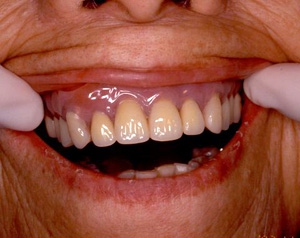

インセラム(オールセラミック)症例①

治療前治療前インセラム(オールセラミック)冠による修復。 主訴は前歯が汚い 金属を使わないオールセラミックでの治療を勧めた。 術前 治療後治療後術後

インセラム(オールセラミック)症例②

治療前治療前術前 治療後治療後術後 歯の尖端の透明感までよく再現できている。